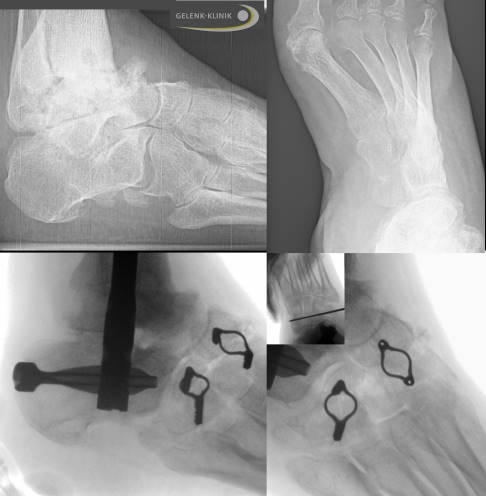

Vorgehen bei den beiden Operationen

Primär ist die schwere Fehlstellung im Sprunggelenk und damit die Fehlstellung des Rückfußes zu behandeln.

Beim 2. Eingriff wurde dann die Fehlstellung der Fußwurzel durch eine Keilresektion aus der Fußwurzel behoben. Die dadurch erreichte gerade Stellung des Fußes beim Stehen und Gehen ist hier besonders wichtig. Die Begradigung und damit die insgesamt bessere Belastung des noch vorhandenen Gelenkes im Fuß sind wichtige Ziele.